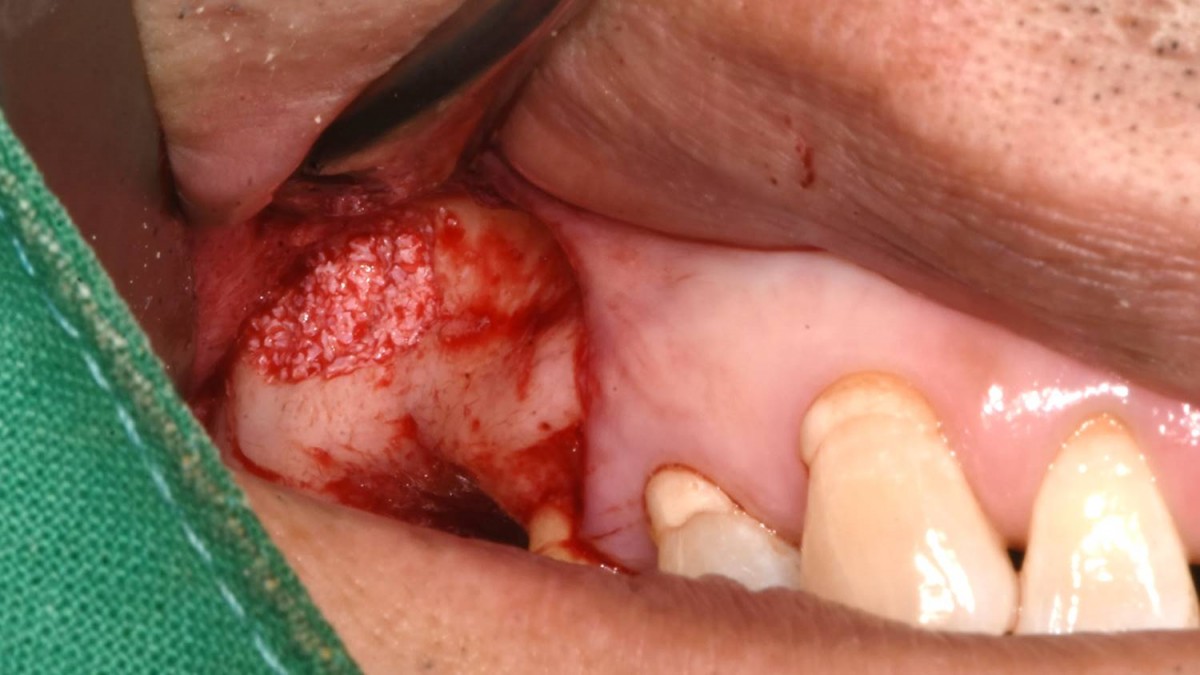

Maxillary Sinus Graft, 2 Implants, Crown Contouring

<GCaks> A 56-year-old male patient had pain-inducing caries, and perio-involved tooth mobility resulted in a tooth fracture at 1st molar. And it was removed months ago. He was a heavy smoker and showed poor oral hygiene.